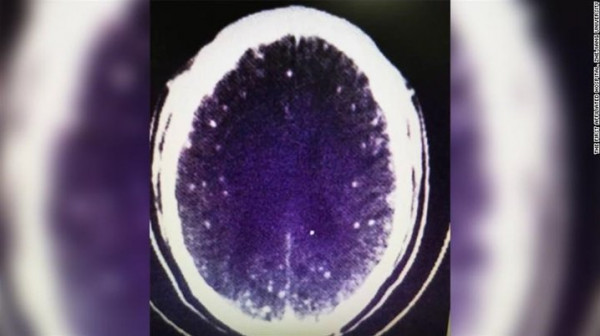

وذهب الرجل إلى أحد الأطباء، الذي طلب القيام ببعض الفحوصات الطبية، فعثر على دودة شريطية في مخ الرجل ناتجة عن تناوله اللحم نيئا وعدم تعريضه إلى المزيد من الحرارة.

وأكد الطبيب أن تلك الدودة هي السبب في إصابة الرجل بتشنجات لأنها عملت على الإصابة بخلل في وظائف المخ، ونصحه بطهي الطعام وتسخينه أكثر وعدم تكرار ما فعله مرة أخرى.